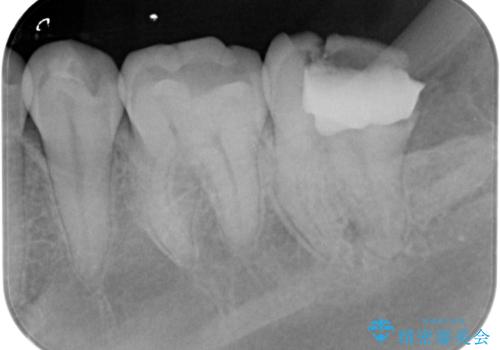

- 歯が痛くなり、他院で治療してもらったところ不信感があり、当院に受診に来られました。

神経をとる処置をされた形跡がありましたがまだ虫歯が残っていたので全て取り除き、壁を立てて根管治療ができる状態にして、根管治療・ジルコニアクラウンで治療を行いました。

虫歯除去、根管治療は拡大鏡やマイクロスコープを用いて治療を行っています。